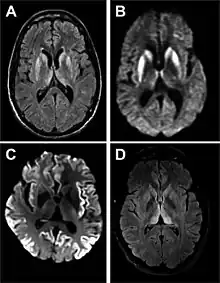

- MRI with diffusion weighted inversion (DWI) and fluid-attenuated inversion recovery (FLAIR) shows a high signal intensity in certain parts of the cortex (a cortical ribboning appearance), the basal ganglia, and the thalami.[36] The most common presenting patterns are simultaneous involvement of the cortex and striatum (60% of cases), cortical involvement without the striatum (30%), thalamus (21%), cerebellum (8%) and striatum without cortical involvement (7%). In populations with a rapidly progressive dementia (early in the disease process), MRI has a sensitivity of 91% and specificity of 97% for diagnosing CJD.[43] The MRI changes characteristic of CJD may also be seen in the immediate aftermath (hours after the event) of autoimmune encephalitis or focal seizures.[36]

Brain MRI is the most useful imaging modality for changes related to CJD. Of the MRI sequences, diffuse-weighted imaging sequences are most sensitive.[49] Characteristic findings are as follows:

- Focal or diffuse diffusion-restriction involving the cerebral cortex and/or basal ganglia. The most characteristic and striking cortical abnormality has been called "cortical ribboning" or "cortical ribbon sign" due to hyperintensities resembling ribbons appearing in the cortex on MRI.[50] The involvement of the thalamus can be found in sCJD, is even stronger and constant in vCJD.[51]

- Varying degree of symmetric T2 hyperintense signal changes in the basal ganglia (i.e., caudate and putamen), and to a lesser extent globus pallidus and occipital cortex.[47]

| Signal hyperintensity in the caudate nucleus and putamen on diffusion-weighted and FLAIR MRI | Often present | Often absent |

| Pulvinar sign-bilateral high signal intensities on axial FLAIR MRI. Also posterior thalamic involvement on sagittal T2 sequences | Not reported | Present in >75% of cases |